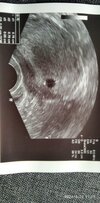

Kochana, nie martw się na zapas... U mnie 5+6 nawet nie było pęcherzyka żółtkowego widać. Wszystko będzie ok. Ciąża się rozwija przecież.Na pewno wszystko jest ok!

Staram się myśleć pozytywnie ale wiesz jak jestmasz zdjęcie? I Jeśli oczywiście chcesz pokazać![]()

A u ciebie było już widać zarodek? Wybacz niepamietamJa też mam tyłozgięcie macicyi też mam dziś 6+0. Byłaś już wcześniej na wizycie czy to Twoja pierwsza?